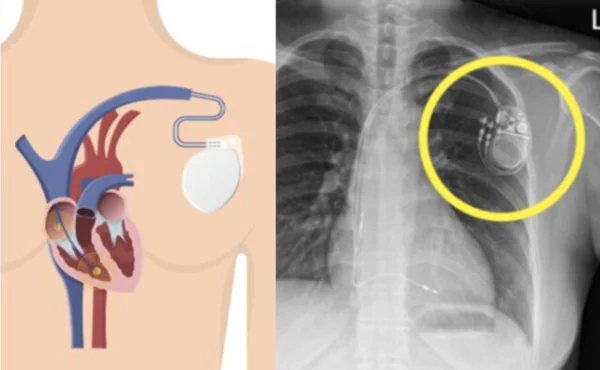

미국 병원에 3일 입원하고, 병원비 3억원 나옴